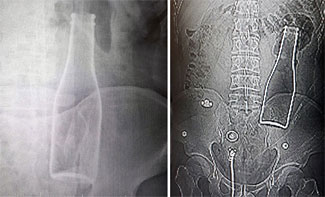

Karın ağrısı için hastaneye gitti vücudunda şişe çıktı